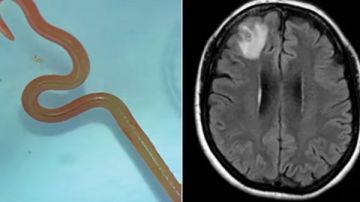

نجح فريق طبي في الصين في إنقاذ حياة رجل بعد إجراء جراحة دقيقة أسفرت عن إزالة دودة حية طولها نحو 18 سنتيمتراً من دماغه، في واقعة نادرة أثارت دهشة كبيرة وأثارت جدلاً واسعًا، وفقًا لما نشره موقع Oddity.

في الشهر الماضي، تفاقمت حالته بشكل حاد، حيث تعرض لنوبات صرع مفاجئة وظهرت رغوة في فمه وفقد وعيه بشكل مفاجئ. بعد فحصه مرة أخرى، اكتشف الأطباء وجود طفيلي حي داخل دماغه. خلال عملية دقيقة استمرت عدة ساعات، تمكن الجراحون من استخراج دودة بيضاء طويلة، كانت لا تزال تتحرك أثناء إخراجها، ما أثار الدهشة بين الفريق الطبي.

الأطباء أوضحوا أن العدوى التي أصيب بها المريض تُعرف باسم 'داء السبارغانوزيس'، وهو مرض طفيلي نادر ينتقل عبر يرقات الدودة الشريطية الموجودة عادة في الثعابين والضفادع والطيور. ويعتبر تناول اللحوم النيئة أو غير المطهوة جيدًا العامل الرئيسي للإصابة بهذا الطفيل، الذي قد يستقر في الدماغ ويسبب أعراضًا عصبية خطيرة تصل أحيانًا إلى الوفاة.